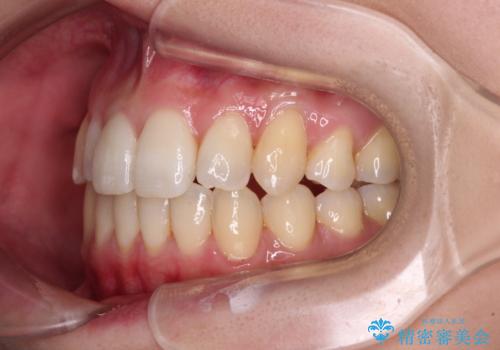

補助装置を併用したインビザラインでの八重歯の抜歯矯正

- 八重歯と奥歯の咬み合わせを気にして来院された患者様です。

インビザラインによる矯正治療を希望されたため、八重歯改善のための抜歯矯正部分は補助装置を併用し、その後はインビザラインにて行うこととしました。

下顎の右側変位が顕著であったため、ワイヤー矯正の方が咬み合わせは改善しやすいのですが、ある程度は時間がかかっても良いとのことであったので、インビザラインにて矯正治療を行うこととしました。

骨格的に下顎が右側に変位していたため、上下正中を合わせることは困難であることは分かっていました。それでも、なるべく合わせるようにとしたため、治療期間は長期間となりました。

長期間とはなりましたが、咬み合わせが改善され、患者様には大変満足していただきました。